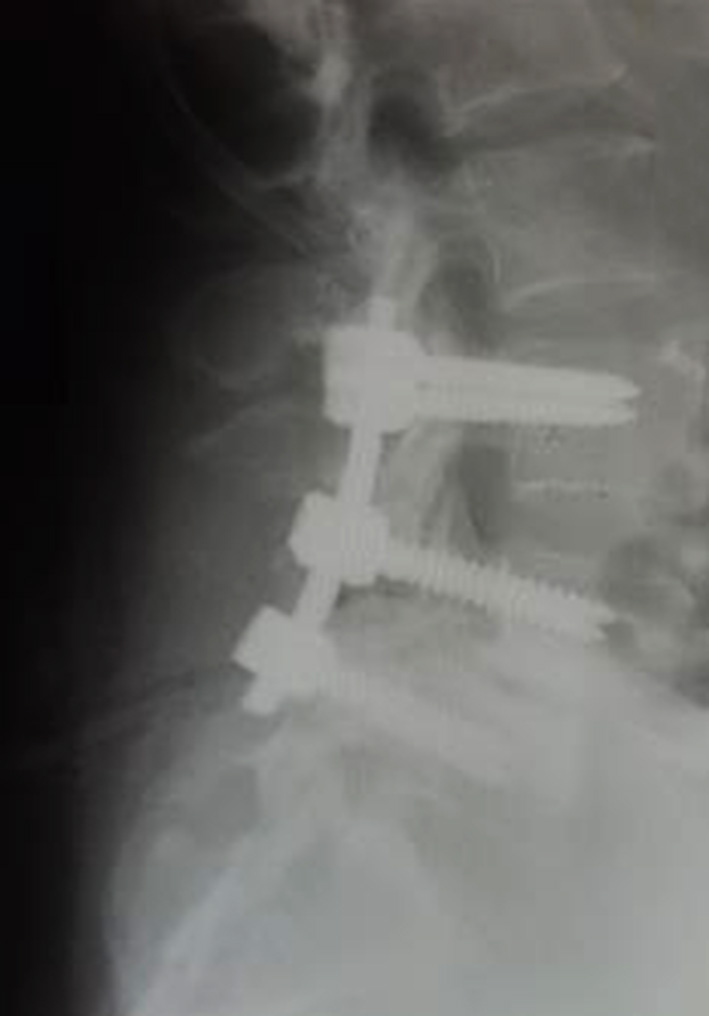

The clinical study involved 21 patients (15 women and 6 men), aged 32 to 68 years (median age – 56 (50; 65) years), divided into three groups: study group (n=4), where the author's technique of MIPIVS was applied (patent application No. a202302383 of 18.05.2023) (Fig. 3); comparison group (n=10), where the standard MIPIVS technique was used (Fig. 4); control group (n=7), where other interbody fusion techniques were employed (Fig. 5) .

Fig. 5. Radiographic control before and after surgery using alternative methods of lumbar interbody spinal fusion